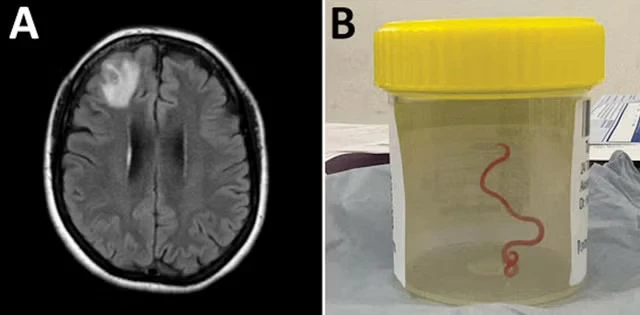

Các bác sĩ ở Úc phẫu thuật thành công một trường hợp có giun tròn dài 8 cm ký sinh trong não người. Bệnh nhân là một phụ nữ Úc 64 tuổi. Vào thời điểm lấy ra khỏi não bệnh nhân, con giun vẫn còn sống.

Con giun được các bác sĩ Úc lấy ra từ não của một bệnh nhân 64 tuổi. Ảnh: EMERGING INFECTIOUS DISEASES |

Trường hợp trên được trình bày trong nghiên cứu của ĐH Quốc gia Úc và Bệnh viện Canberra (Úc), được đưa ra vào ngày 29-8. Thông qua xét nghiệm, các nhà khoa học xác nhận con giun trên là Ophidascaris robertsi - một loại giun tròn thường có ở loài trăn.

Đến năm 2022, các bác sĩ cho biết bệnh nhân rơi vào tình trạng hay quên và trầm cảm. Kết quả chụp cắt lớp sau đó cho thấy bệnh nhân bị "một tổn thương ở thùy trán bên phải của não".